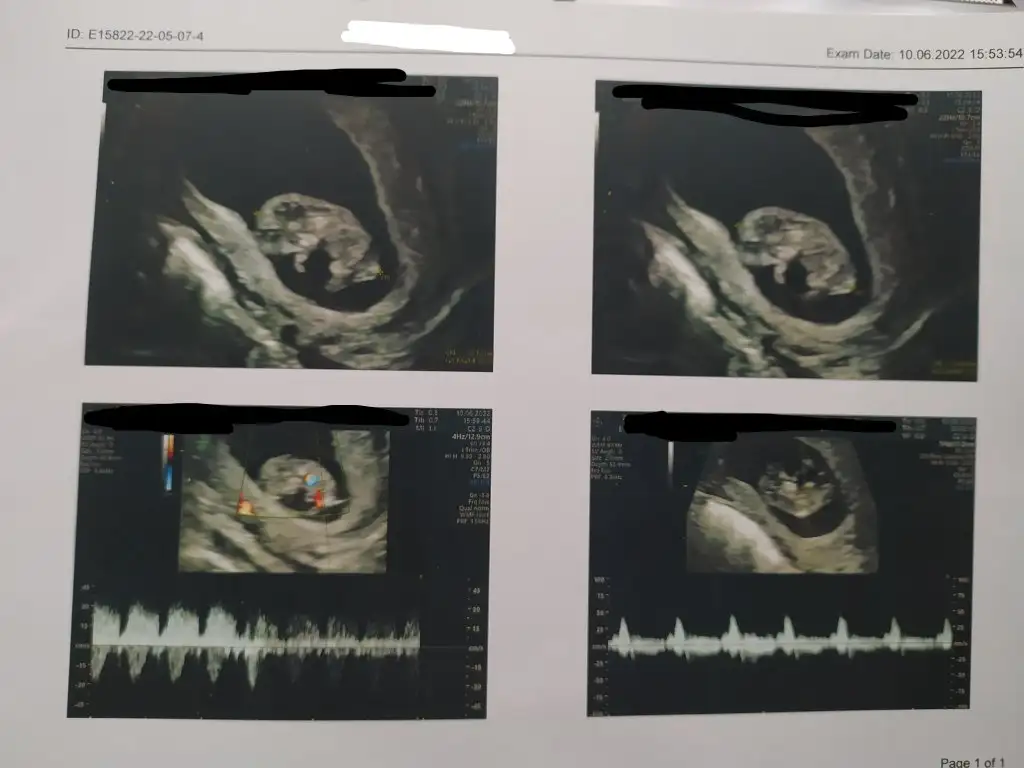

Bu erkek oluyor galiba değil mi ?12+1 çıktı

Kiz olunca üç çizgi oluyormus bunda 2 var sanki

5 ve 14. haftaya kadar olan ultrason fotolarınızı paylaşın. Vajinadan mı yoksa karından mı çekildiğini ve kaç haftalık olduğunu da mutlaka belirtin.

Benim kızmış canımkuzucum erkek bebiş gibi görünüyor hakkında hayırlısı :) geri dönüş yapmayı unutma

bu vajina dan mı?